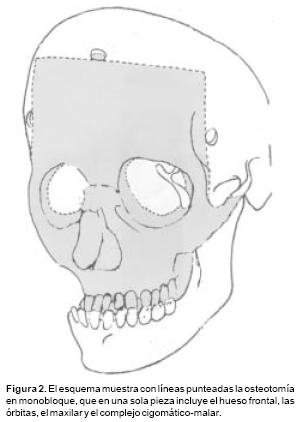

Las osteotomías a utilizar se diseñan previamente en las reconstrucciones tridimensionales obtenidas con la T.A.C., y ésta varía de acuerdo a la deformidad de cada paciente. Las más utilizadas son: osteotomías fronto–orbitarias bilaterales (Figura 1), osteotomía tipo monobloque (Figura 2) y osteotomía fronto–orbito–malar unilateral (Figura 3). La osteotomía seleccionada se dibuja sobre la estructura esquelética disecada utilizando violeta de genciana. En este momento se selecciona 2 o 3 sitios sobre el hueso frontal para las craneotomías. Y una vez completadas estás, se realiza una disección intracraneana muy limitada que sigue las líneas de las osteotomías en el área frontal y orbitaria, creando una serie de túneles intracraneanos y preservando la mayoría de los puentes vasculares entre las meninges y el hueso frontal. El mismo procedimiento se utiliza para el techo orbitario. A través de los túneles se introducen tiras de gasas y separadores muy finos que permiten la realización de las osteotomías con sierras oscilatorias, sin daño a las estructuras subyacentes. Con un endoscopio rígido de visión directa se verifica la hemostasia y la integridad de las meninges luego de realizar las osteotomías. Así mismo bajo visión endoscópica se realiza una cuidadosa disección del área de la Crista Galli y de las alas menores del esfenoides en su unión con la órbita y el frontal, lo que permite completar las osteotomías a nivel central y lateral y la movilización de toda la estructura ósea a avanzar. En los casos de monobloque, la línea de osteotomía se continúa de la pared lateral orbitaria a la unión pterigomaxilar y sobre el piso y la pared medial de la órbita. En estos casos la disyunción con pinzas de Rowe del área pterigomaxilar, se hace necesario a fin de avanzar en un verdadero monobloque el maxilar unido a las órbitas y al hueso frontal (Figura 2).

Para los avances frontoorbitarios el vector distraccional más utilizado es el tipo horizontal. En estos casos la osteotomía incluye el hueso frontal y la órbita hasta su ángulo infero–externo. Aquí el distractor idealmente se apoya 5 mm., por encima del reborde orbitario superior a fin de lograr más avance de la frente y un avance gradual de la órbita (Figura 4). Para los avances en las osteotomías tipo monobloque, se utilizan dos pares de distractores:

a Los que avanzan el tercio medio de la cara, que generalmente utilizan un vector distraccional oblicuo, de arriba hacia abajo (Figura 5). El distractor se apoya en la unión de la órbita y el hueso malar, o en la cara posterior del malar. Esta dirección de distracción avanza el maxilar, los malares y la mitad inferior de las órbitas recreando la curva de crecimiento, que el tercio medio de la cara normalmente realiza durante el desarrollo y evita la producción de alteraciones oclusales como las graves mordidas abiertas anteriores u otras, b Los que avanzan el hueso frontal y el reborde supraorbitario, son un par de distractores que tienen un vector horizontal. Especialmente en niños con edades entre los 9 y los 14 meses durante el avance, es importante evitar la fractura de la unión frontoorbitaria, debido a que ésta es una unión ósea muy lábil en estas edades y la fuerza producida por estos distractores durante su activación puede producir fácilmente esta fractura.